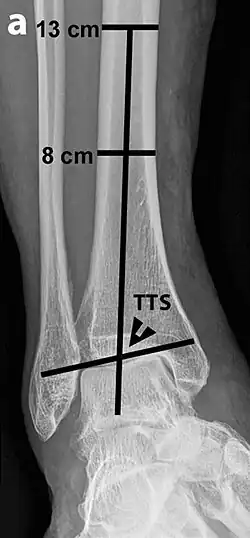

Tibiotalar surface angle (TTS)

Varus or valgus deformity, if suspected, can be measured with the frontal tibiotalar surface angle (TTS), formed by the mid-longitudinal tibial axis (such as through a line bisecting the tibia at 8 and 13 cm above the tibial plafond) and the talar surface.[25] An angle of less than 84 degrees is regarded as talipes varus, and an angle of more than 94 degrees is regarded as talipes valgus.[26]